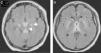

Varón de 23 años, con antecedentes de pancreatitis biliar hace un mes y colecistectomizado hace una semana, presenta historia de 2 días de fiebre, mareo, confusión y debilidad muscular marcada en miembros inferiores por lo que ingresa a planta de medicina interna. En la exploración física se observa signos de deshidratación y se descartó complicación posquirúrgica. Tomografía de cerebro y abdomen normal. Al día siguiente evoluciona con somnolencia, cuadriparesia, hiporreflexia seguido de estupor e inestabilidad hemodinámica por lo que ingresa a Unidad de Terapia Intensiva; se inició tratamiento empírico con meropenem y vancomicina. Se realiza resonancia magnética de cerebro que reveló lesiones hiperintensas en tronco cerebral, fórnix y tálamo bilateral (figs. 1 A y B, flechas blancas), sin desplazamiento de línea media. El diagnóstico diferencial incluyó vasculitis, herpes, tuberculosis y toxoplasmosis. El estudio citológico bioquímico de líquido cefalorraquídeo se mostró inespecífico y en estudio de biología molecular por PCR se detectó ARN del virus del Zika. Se inicia tratamiento inmunomodulador con inmunoglobulina humana (IgG), a los 5 días se realiza nueva resonancia magnética que evidencia progresión de lesiones a pedúnculos cerebrales y núcleos de la base (figs. 2 C y D, fechas blancas) seguido de disfunción orgánica múltiple y muerte.